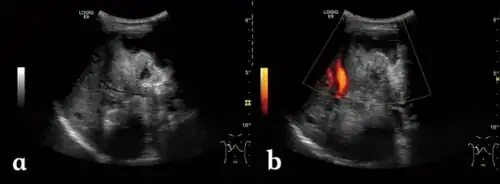

a) Irregular type heterogeneous mass lesion b)no obvious blood flow signal